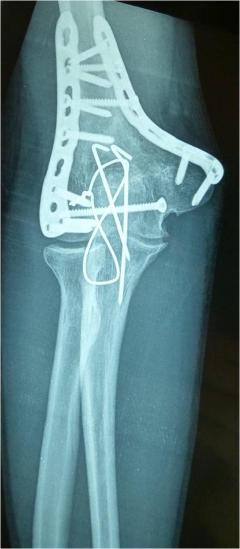

Περίπτωση 1ου ασθενούς

4 χρόνια μετά το χειρουργείο